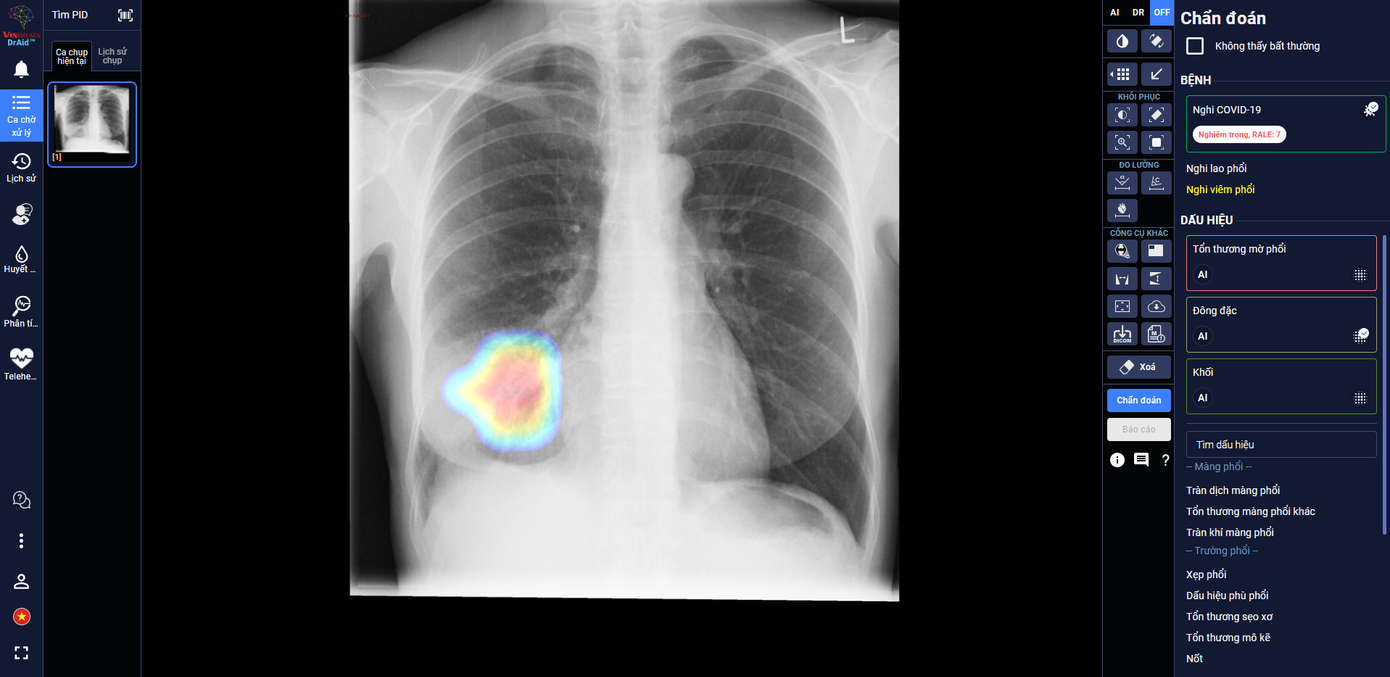

| DrAid giúp bác sĩ theo dõi mức độ tổn thương phổi ở một bệnh nhân F0 trên ảnh X-quang phổi |

Trong các bệnh viện thu dung điều trị COVID-19, DrAid cho COVID-19 giúp các bác sĩ đánh giá mức độ tổn thương phổi của bệnh nhân COVID-19 qua các ngày, từ đó đưa ra các chỉ định điều trị kịp thời và hiệu quả cho bệnh nhân.